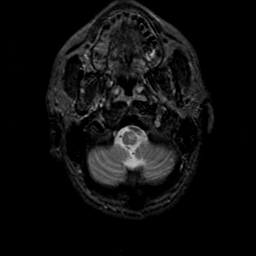

MR Study #23, January 26, 1992 -- Slice #4

[Home][Help][Clinical][Tour 1][Tour 2] Slice 4